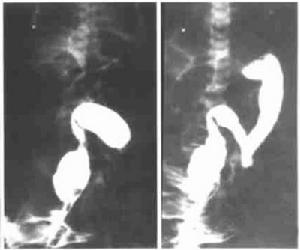

4、鋇劑灌腸X線拍片對診斷病變在直腸、乙狀結腸的病例,準確率達90%以上。病變部位可見直腸持續性狹窄,呈漏斗狀與擴張的腸段相接,動態像顯示結腸蠕動強烈而規則,排鋇後由於腸壁和黏膜增厚,見腸腔內有明顯皺褶,類似正常空腸皺褶,被稱為所謂的“結腸空腸化”改變。多數患兒不能及時排鋇,觀察排鋇功能是對新生兒巨結腸的重要診斷。並髮結腸炎時,X線可見近端擴張結腸的輪廓模糊,外形僵直,有多數不規則的毛刺突出。